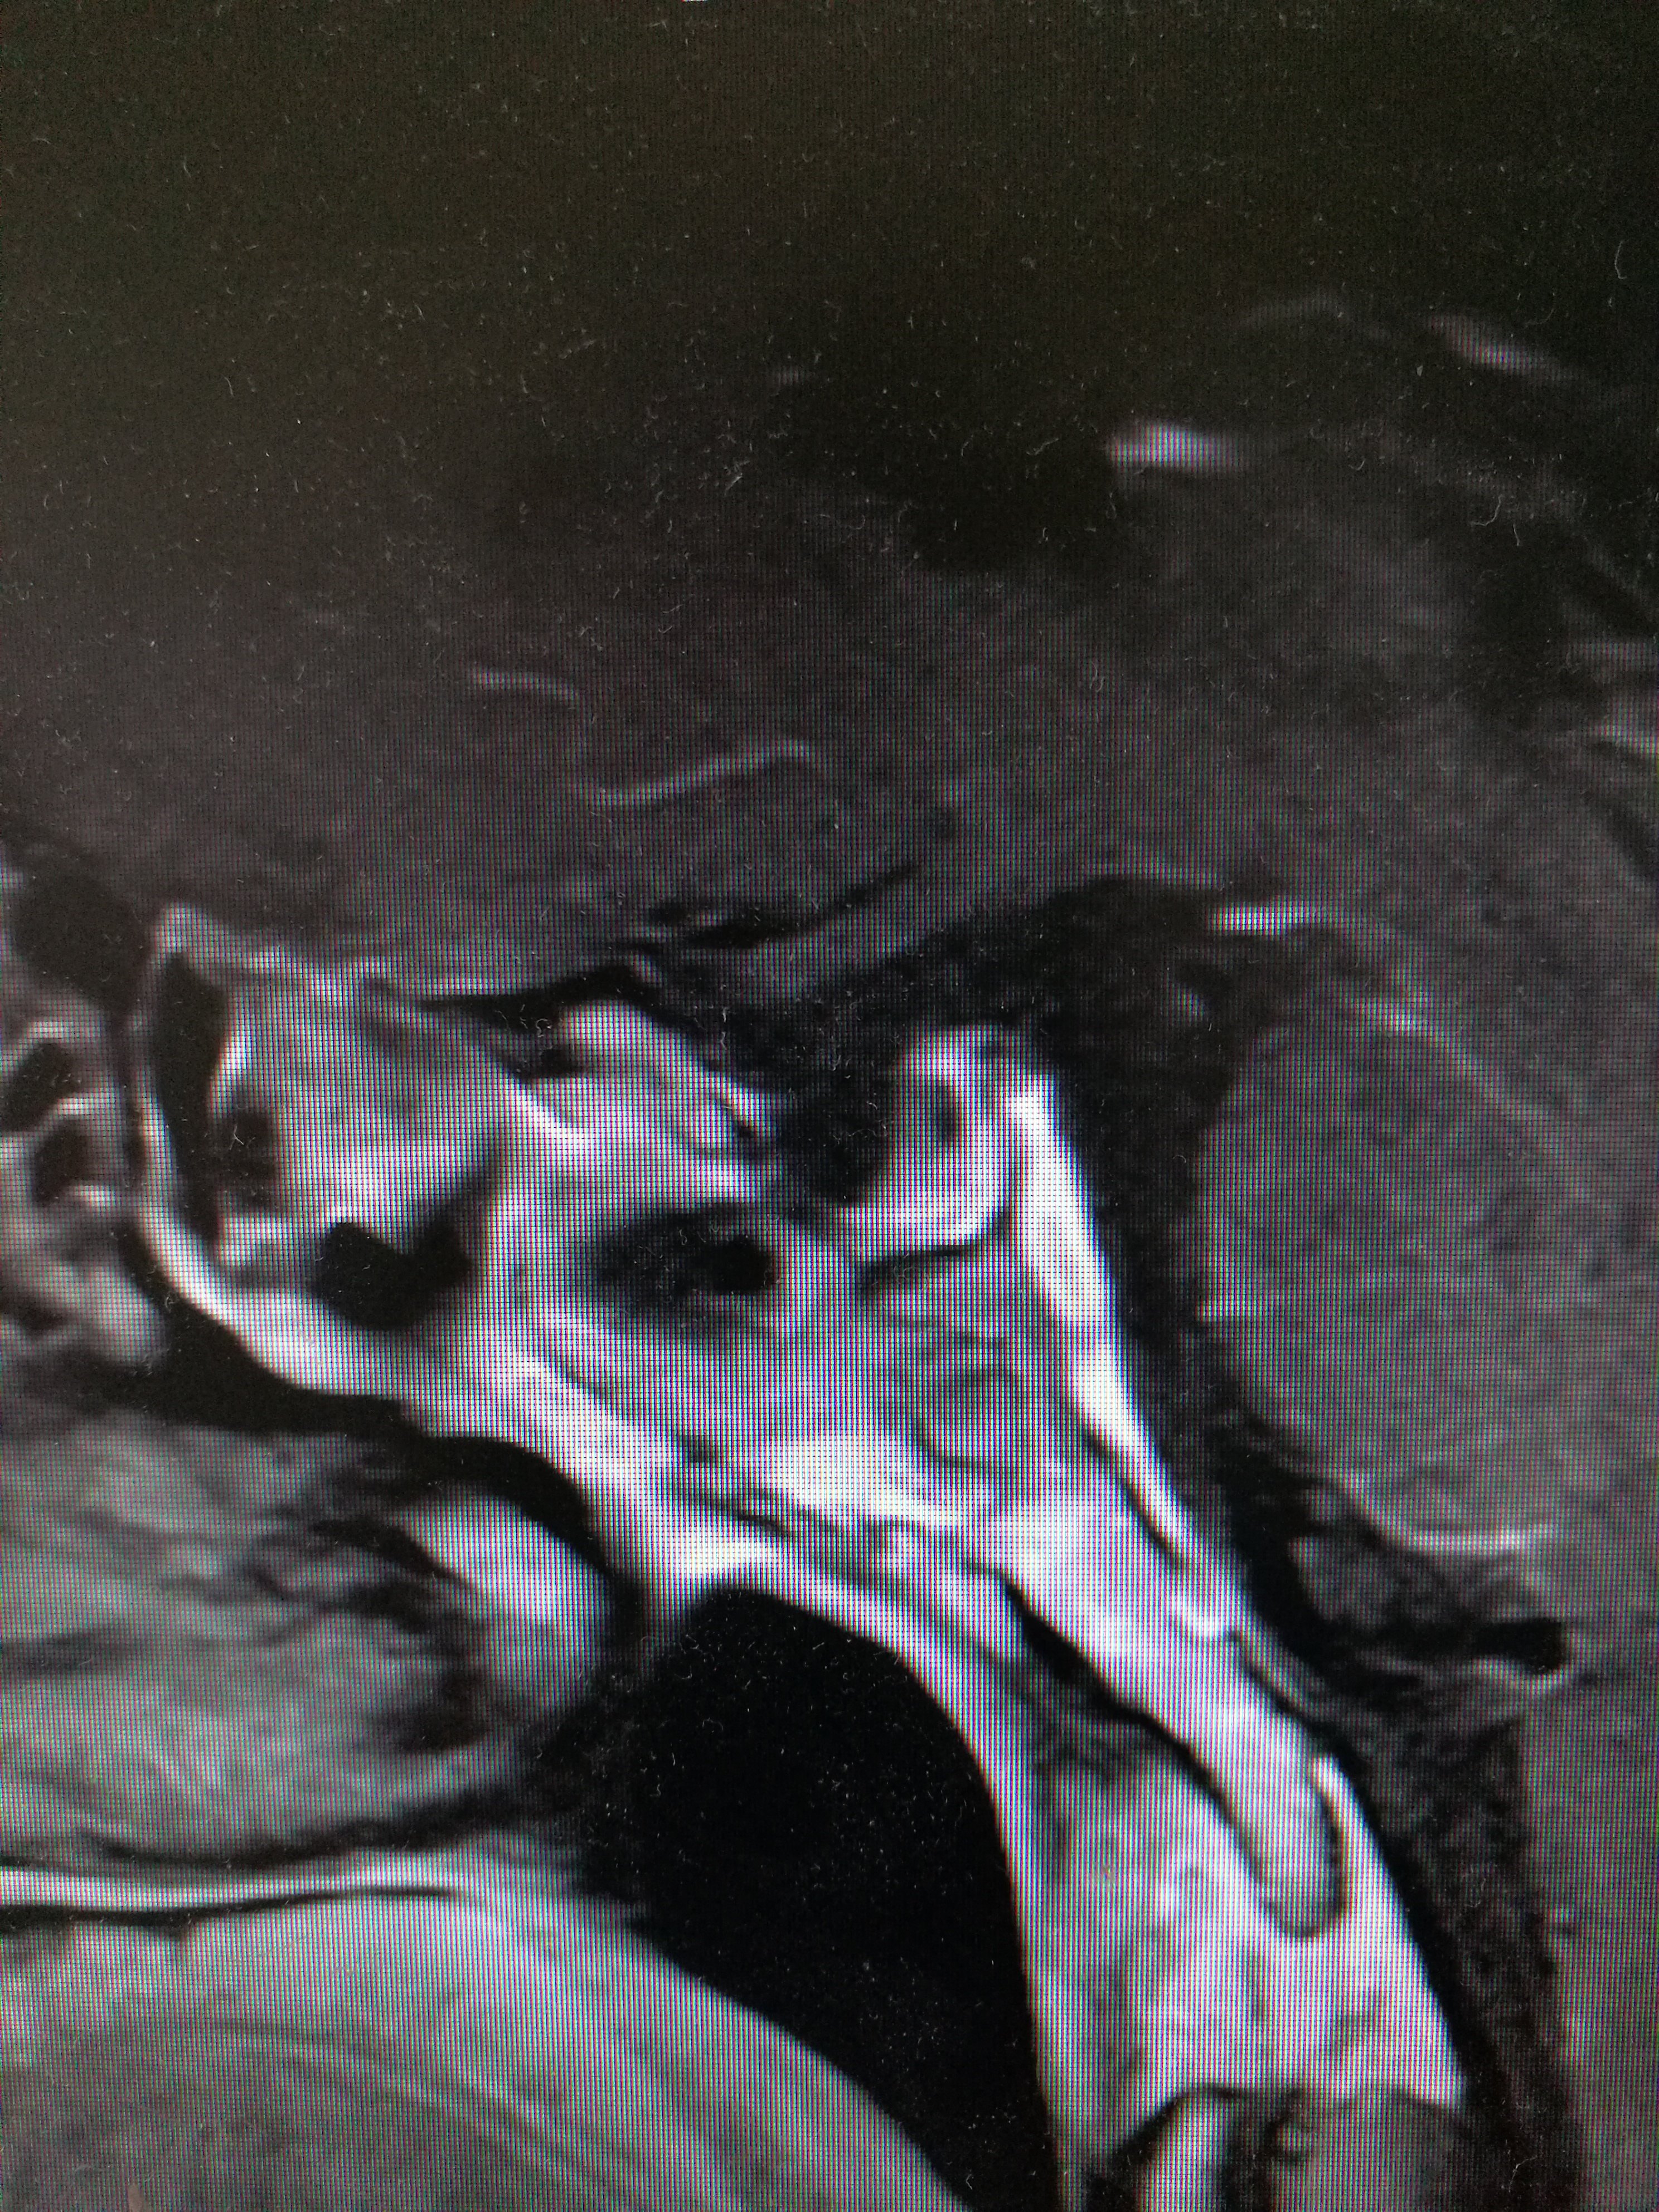

经鼻内镜下修复垂体瘤术后迟发的脑脊液鼻漏(

2976x3968 - 2958KB - JPEG